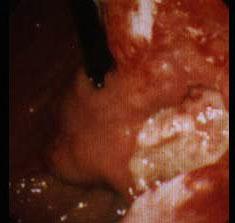

问题 胃癌的好发部位依次是 ( )

选项 A、胃窦部、贲门部、胃体 B、贲门部、胃体、胃窦部 C、胃体、胃窦部、贲门部 D、贲门部、胃窦部、胃体 E、胃窦部、胃体、贲门部

答案 A